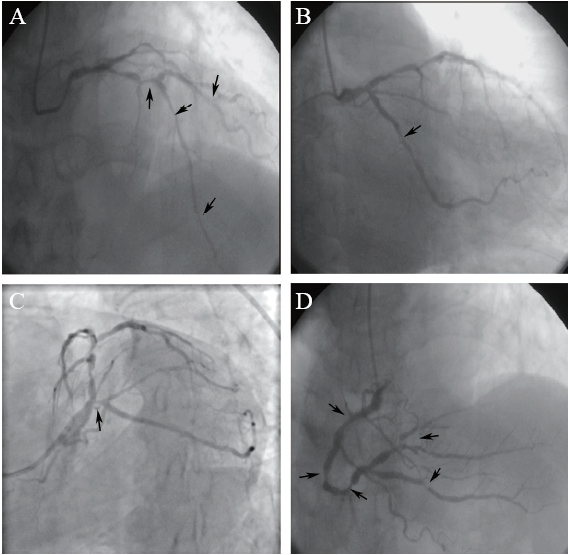

图2 一例NSTEMI患者行右冠状动脉药物球囊扩张术CAG图

A:右冠状动脉药物球囊扩张术前;B、C:药物球囊(3.0 mm×26.0 mm、3.0 mm×26.0 mm、3.5 mm×26.0 mm) 治疗过程;D:药物球囊治疗术后

图3 一例NSTEMI患者行回旋支药物球囊扩张术CAG图

A:回旋支药物球囊扩张术前;B、C:药物球囊(2.75 mm×26.00 mm、3.0 mm×17.0 mm)治疗过程;D:药物球囊治疗术后

患者行CAG示左主干+三支病变(图1),SYNTAX评分64分,建议首选冠状动脉搭桥术,患者及家属拒绝冠状动脉搭桥术。患者频繁发作胸痛症状,心肌梗死指标高,冠心病系亟待解决的主要问题,结合患者血小板水平及以后长期双联抗血小板聚集(DAPT)治疗的风险,适宜选择抗血小板治疗时间短、出血风险低的策略,因此首选药物球囊扩张术。术前先加用双联抗血小板聚集药物(阿司匹林100 mg/d+氯吡格雷75 mg/d),同时应用升血小板聚集药物(重组人血小板生成素+重组人IL-11皮下注射),并备血及血小板,治疗3 d后复查血常规提示血小板较前无明显下降。于2020年1月13日在局部麻醉下分别对右冠状动脉及回旋支病变行药物球囊扩张术,术中先对病变充分预扩张,右冠状动脉先后应用3.0 mm×26.0 mm、3.0 mm×26.0 mm、3.5 mm×26.0 mm的药物球囊,回旋支先后应用2.75 mm×26.00 mm、3.0 mm×17.0 mm的药物球囊,对病变进行扩张,术后可见右冠状动脉、回旋支病变程度较前明显减轻(图2、3),紫杉醇药物球囊均由德国贝朗公司生产。

术后患者胸痛程度及发作频率较前明显缓解,多次复查血常规提示血小板下降不明显,于1月19日复查血常规示血小板31.00×109/L,1月23日复查血常规示血小板34.00×109/L,患者未再发作胸痛,于住院第15日出院。出院后口服拜阿司匹林、氯吡格雷、单硝酸异山梨酯缓释片、曲美他嗪、阿托伐他汀、雷贝拉唑、利可君、咖啡片等药物治疗,术后随访至2020年4月28日,患者未再发作胸闷、胸痛、心悸等不适,复查血常规示血小板51.00×109/L。